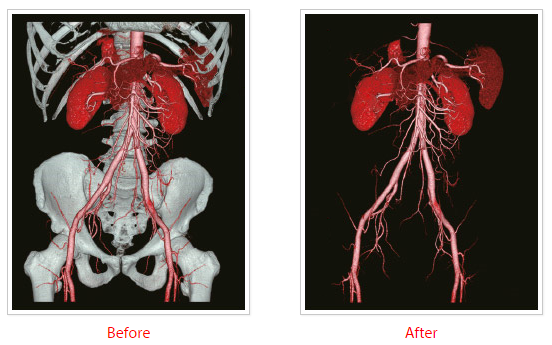

SURESubtraction (Brain/Neck/Ortho) — исследования головного мозга / шеи / ортопедические

Удаление изображения костных структур и кальцифицированных бляшек для повышения точности КТА. Надежные алгоритмы регистрации могут адаптироваться к широкому диапазону анатомических особенностей и возможных движений.